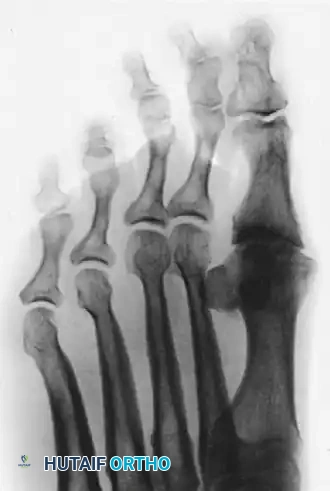

In many instances, hallux rigidus presents bilaterally, necessitating a comprehensive evaluation of the contralateral foot to plan for staged or concurrent interventions.

Image

Anteroposterior view of bilateral hallux rigidus, highlighting the symmetric nature of the degenerative process in susceptible individuals.